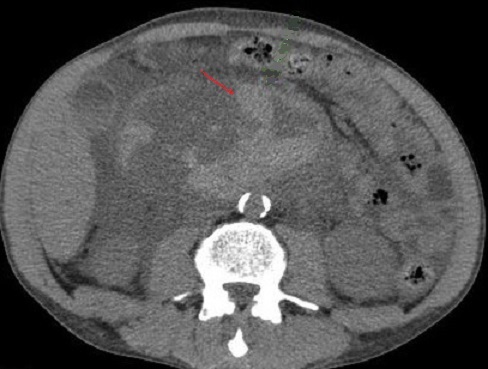

Les calcifications souvent

parenchymateuse mais parfoi peut etre canalaire (

fleche rouge ). Dans ce cas image de dilatation des

canal biliaire peut en voyait . Image

radiologique TDM d'une pancreatite chronique +

calcul du canal pancreatique en coupe axiale |